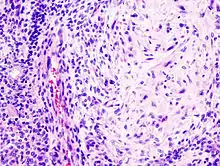

O adenoma pleomórfico é um tumor tipicamente encapsulado e bem circunscrito. Entretanto, a cápsula pode ser incompleta ou exibir infiltração por células tumorais. Essa falta de encapsulação completa é mais comum nos tumores de glândula salivar menor, especialmente ao longo da porção superficial dos tumores do palato, abaixo da superfície epitelial.

O tumor é composto de uma mistura de epitélio glandular e células mioepiteliais permeados por um fundo semelhante ao mesênquima. A proporção dos elementos epiteliais e do componente semelhante ao mesênquima é altamente variável dentre os diferentes tumores. Alguns tumores consistem quase inteiramente de um fundo “estromal.” Outros são altamente celulares com poucas alterações ao fundo.

Geralmente o epitélio forma ductos e estruturas císticas, ou pode ocorrer na forma de ilhas ou cordões celulares. As células escamosas produtoras de ceratina ou células produtoras de muco também podem ser vistas. As células mioepiteliais geralmente compõem uma grande porcentagem das células tumorais e exibem uma morfologia variável, podendo apresentar-se como células anguladas ou fusiformes. Algumas células mioepiteliais são arredondadas e possuem núcleo excêntrico e citoplasma eosinofílico hialinizado, lembrando plasmócitos. Estas células mioepiteliais plasmocitoides características são mais proeminentes nos tumores oriundos de glândulas salivares menores.

Acredita-se que as alterações características observadas no parênquima sejam produzidas pelas células mioepiteliais. Um extenso acúmulo de material mucoide pode ocorrer por entre as células tumorais, resultando em um aspecto mixomatoso. Nestas áreas, a degeneração vacuolar das células pode produzir uma aparência condróide. Em muitos tumores, o parênquima exibe áreas de alteração eosinofílica e hialinizada. Algumas vezes, podem ser vistos tecido gorduroso ou osteóide.